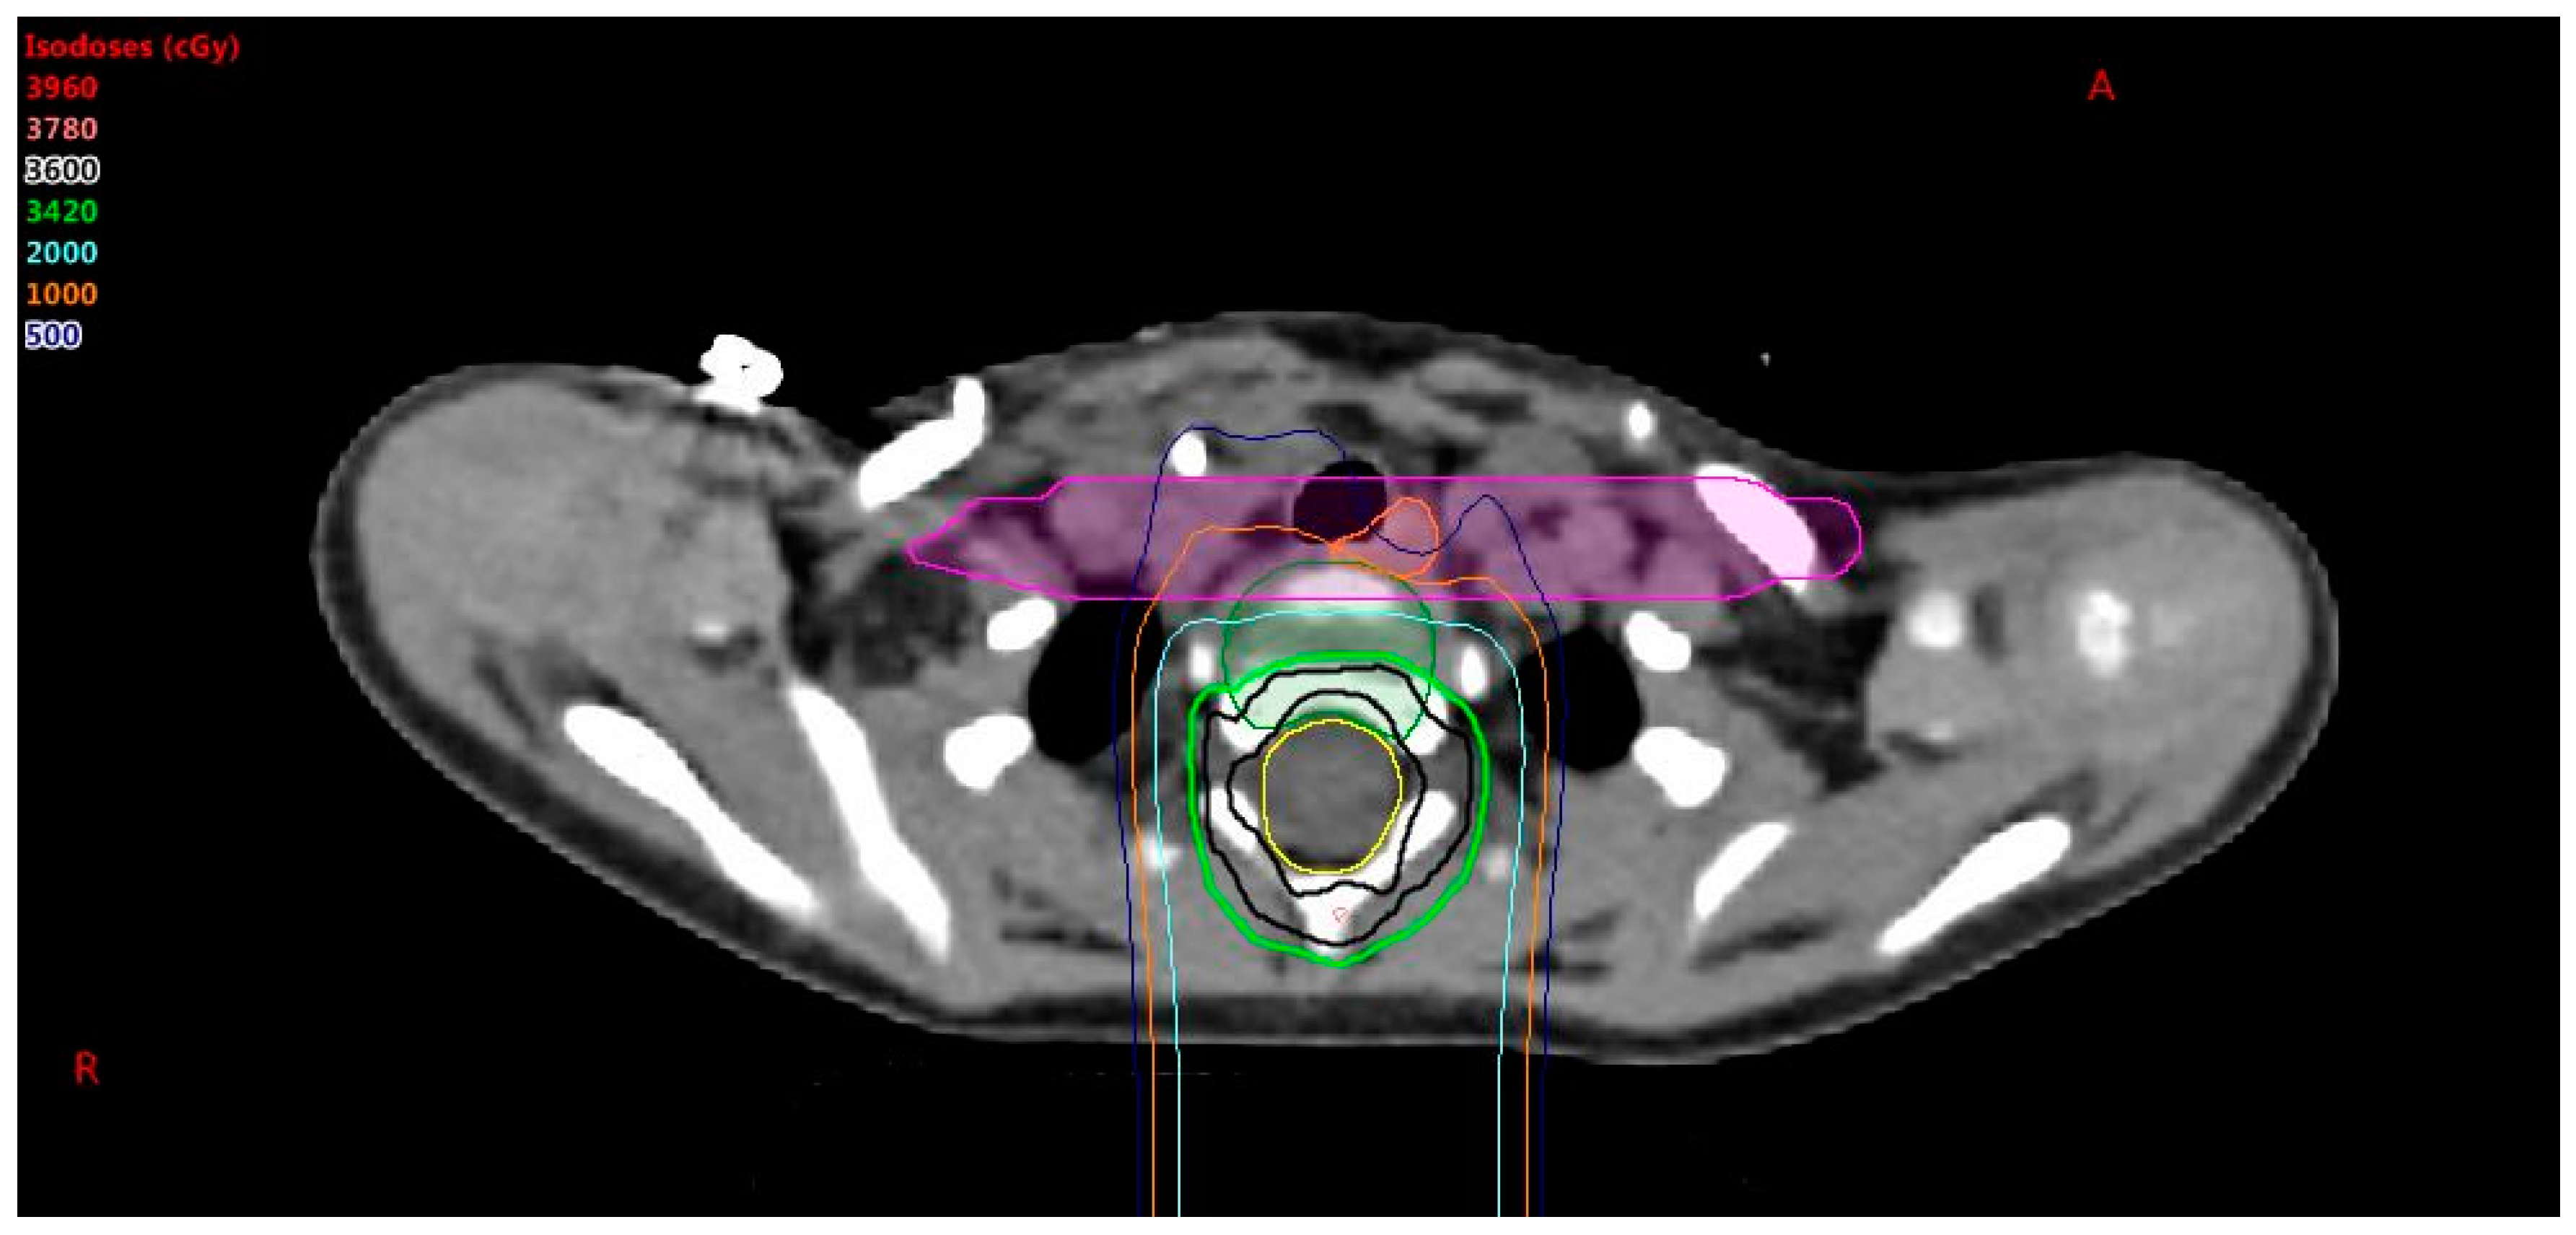

Since the CTV in the spine typically follows the nerve roots, the CTV and thus OTV can look scalloped in the coronal plane. The optimizer may try to chase this contour, which frequently leads to undesired hot spots. To mitigate this issue, the margin for the OTV in the spine can be extended in the superior/inferior directions by 10 mm to create a more continuous target volume. An example is shown in Figure 1. This final OTV structure, including the spine expansion and de-scalloping, is referred to as the OTV all.

Figure 1. The Clinical Target Volume (CTV) (blue) is scalloped. The Optimization Target Volume (OTV) (magenta) is equal to the CTV with a 10 mm expansion in the superior/inferior direction.